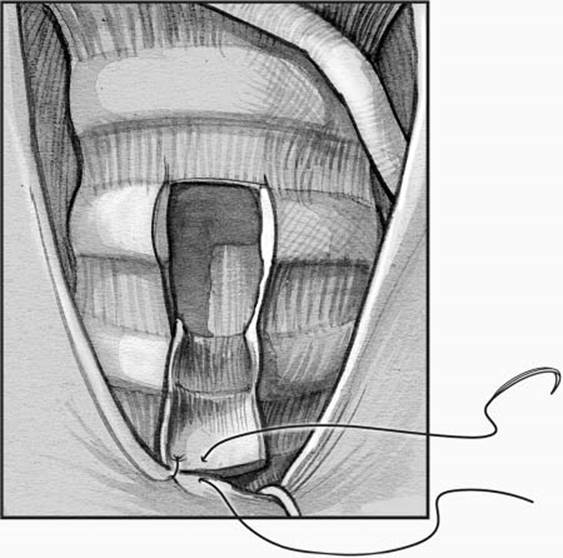

Once the laryngotracheal cartilage is clearly exposed, vertically oriented “stay” sutures are placed on both sides of the midline of tracheal rings 2 to 4 (Fig. 11.2). These sutures can help provide traction during the procedure and help identify the tracheotomy lumen should there be accidental decannulation. The lateral retractors can then often be removed, and the trachea is incised vertically at rings 2 to 4 to enter the airway. A vertical incision has been shown in some studies to have less risk of suprastomal collapse or stenosis than other tracheal incisions.11 If electrocautery is used during the procedure, the inspired oxygen concentration in the anesthesia circuit should be reduced to avoid airway fire.12 With the tracheal lumen well exposed by gentle retraction on the stay sutures, the endotracheal tube is withdrawn under direct view until it lies just proximal to the tracheal incision, and the tracheostomy tube is gently inserted with an obturator. Following connection of the circuit, forceful ventilation is avoided until proper tracheostomy position is confirmed by presence of breath sounds, chest inflation, and end-tidal CO2 on monitors. The tube is usually secured with circumferential cloth neck ties placed and tied with the neck is flexed. Skin sutures, or a combination of sutures and trach ties, are less commonly used.10 Stay sutures are clearly labeled “right” and “left” and secured to the chest. Flexible tracheobronchoscopy may be performed to confirm appropriate positioning of the tracheostomy tube proximal to the carina.

Figure 11.2 Stay sutures (3–0) are placed lateral to the planned incision site through the second and third tracheal cartilages in preparation for vertical tracheotomy incision.

The stay sutures are left in place until the first tracheostomy tube change, usually at 5 to 7 days after the procedure. The sutures can help provide traction and identify the tracheotomy should there be a decannulation. A chest radiograph may be obtained to check the tube position and identify pneumothorax, but the need for routine postoperative chest films has recently been questioned for asymptomatic patients.13